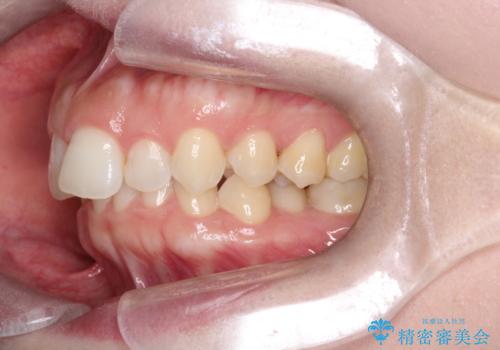

【インビザライン】前歯の凸凹を治したい。

- 前歯の凸凹を主訴に来院されました。

深い噛み合わせも同時に治療を行う計画を立て、インビザラインを使用して歯並びの改善を行うことができました。

叢生改善のために遠心移動とIPRを行なっています。